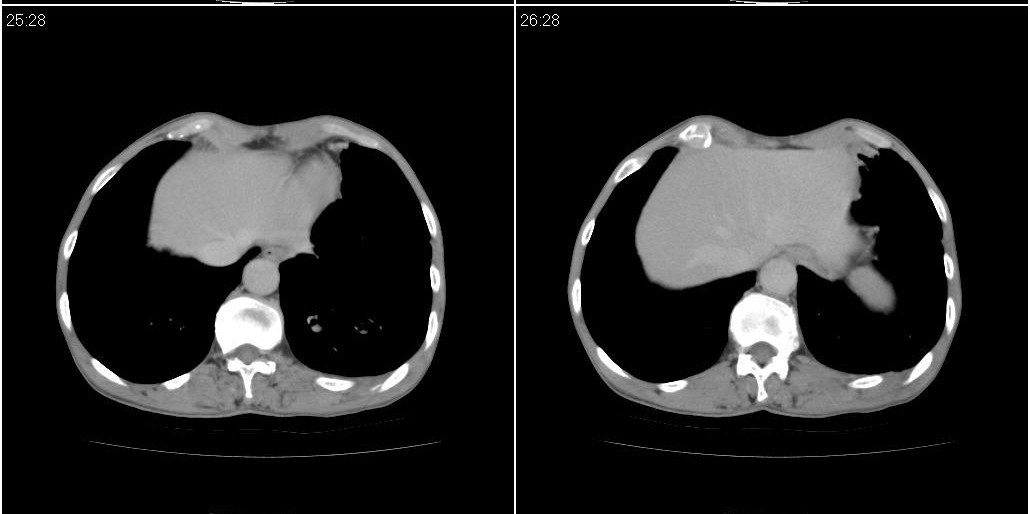

右中肺阻塞性炎症,建议纤支镜!双下支扩感染。

1)右肺中叶慢性炎症并支气管扩张,节段性肺不张。2)两肺下叶支气管扩张。

1)右肺中叶慢性炎症并支气管扩张,节段性肺不张。2)左肺下叶支气管扩张